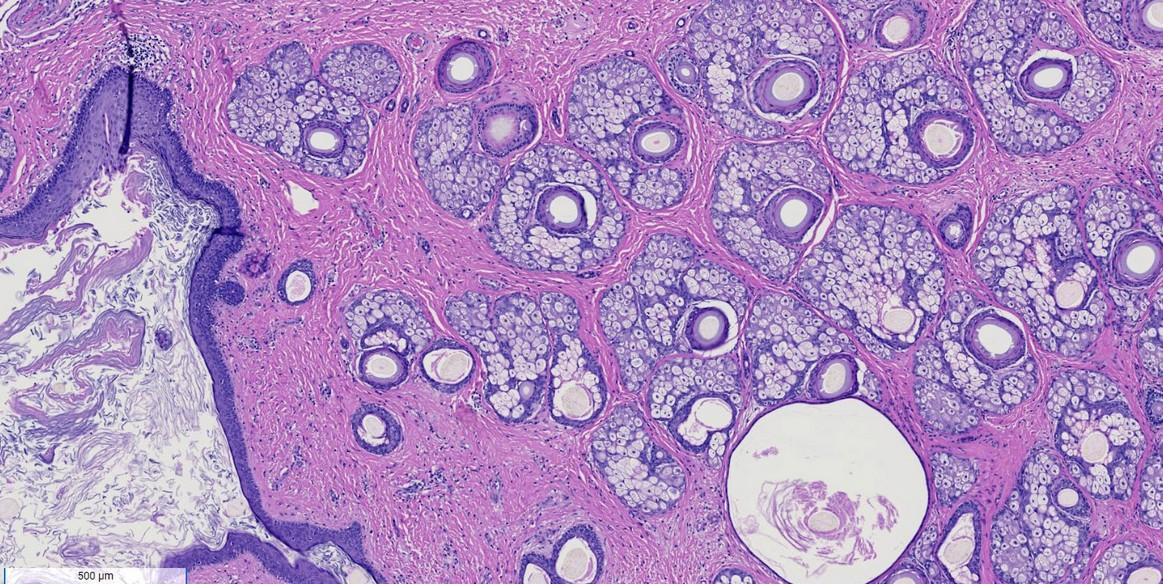

Mature benign teratoma vs immature teratoma (malignant)

Mature tumors often have hair/teeth in them

Grade of tumor can impact treatment

Relies on pathologic assessment of immature neural tissue

IT when treated with chemotherapy, can reemerge as mature teratoma (growing teratoma syndrome)